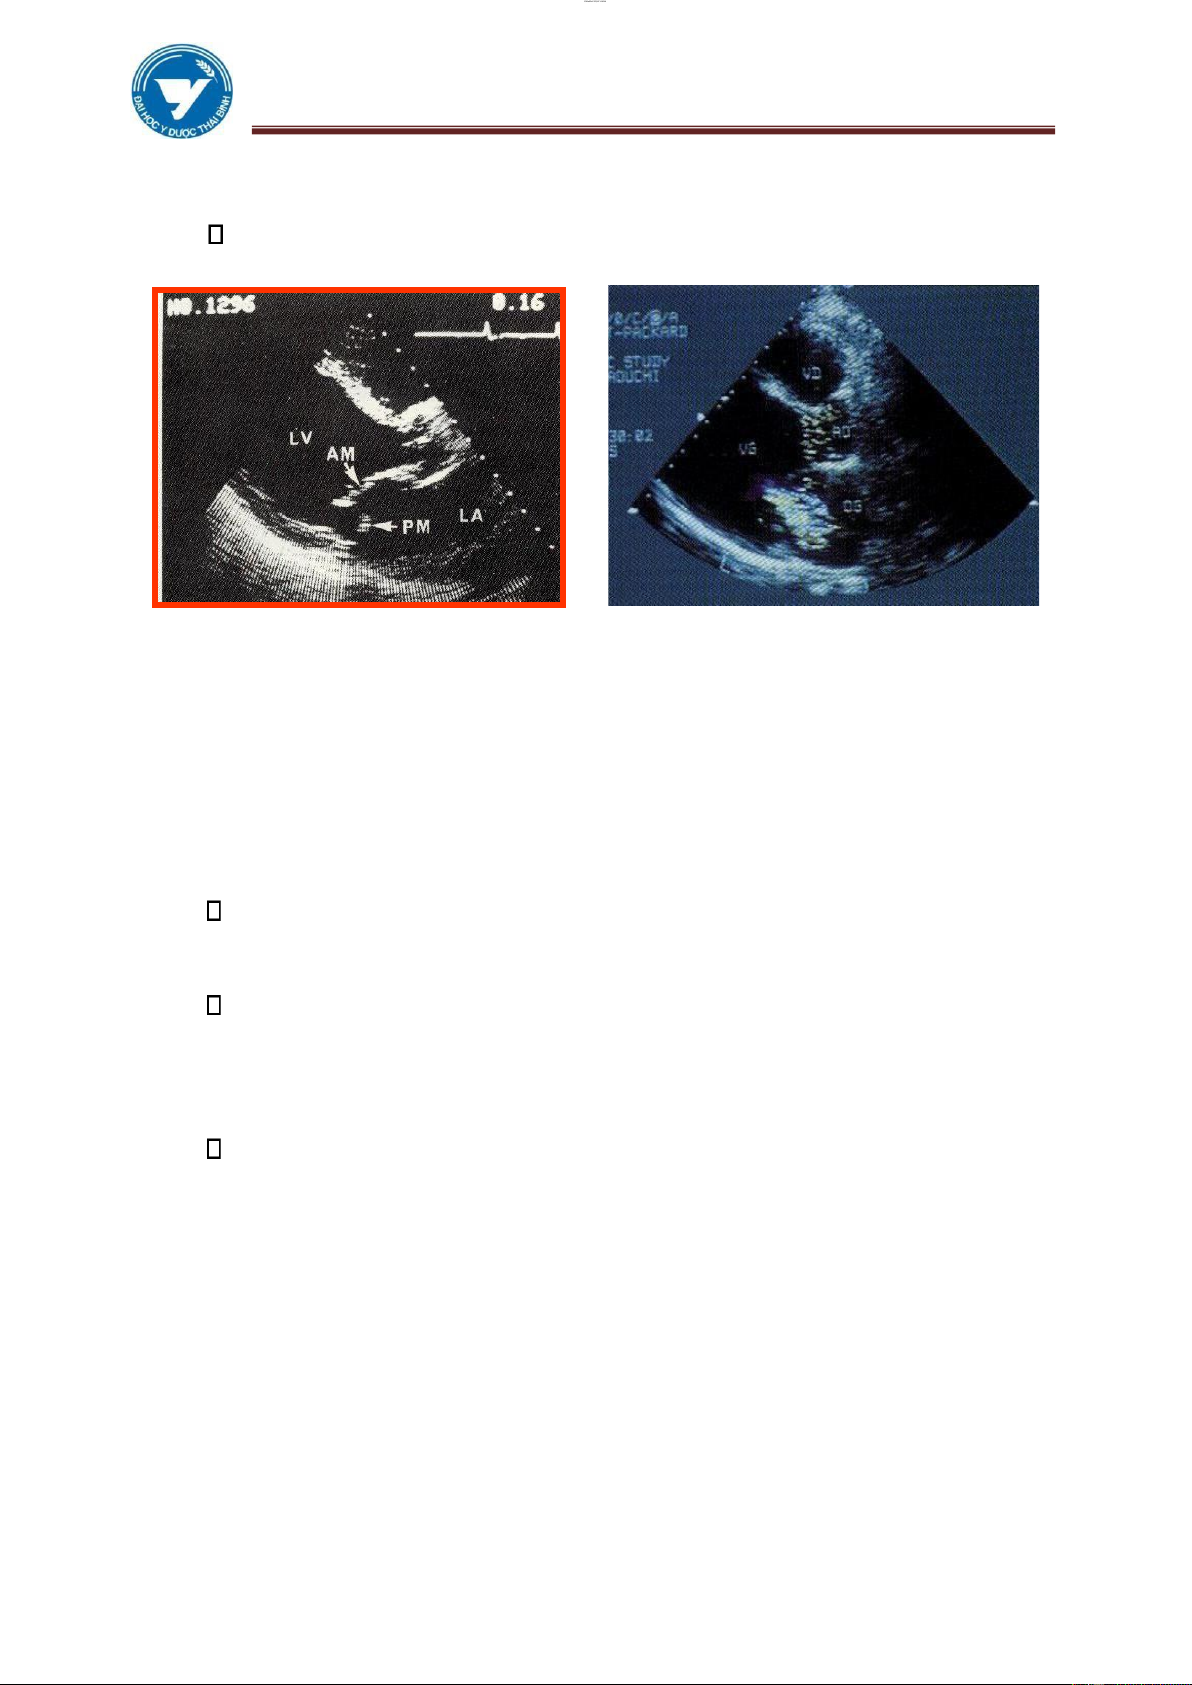

3.2. Hình ảnh siêu âm

Hẹp van 2 lá: Thấy trực tiếp kích thước của lỗ van , xác ịnh tính mềm

mại của các van hay thâm nhiễm, sùi. Thấy nhĩ trái lớn hơn rõ, có thể thấy

ược cục máu ông ở trong buồng tim.

Hở van 2 lá ơn thuần: triệu chứng trực tiếp áng tin cậy, có thể thấy ược dây

chằng (tổ chức dưới van) bị ứt, tăng ộng thất trái, tăng thể tích thất trái.

Hình 3.15. Hẹp van hai lá lOMoAR cPSD| 22014077 lOMoAR cPSD| 45148588